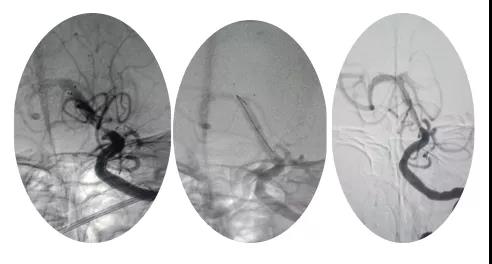

18:30手術(shù)開始,造影為基底動(dòng)脈閉塞,與患者家屬充分溝通,患者家屬同意給予介入取栓治療。共取栓2次,取出少量暗紅色血栓塊。造影示:基底動(dòng)脈有重度狹窄,結(jié)合患者病情演變及造影結(jié)果,考慮為動(dòng)脈粥樣硬化性狹窄。根據(jù)患者造影結(jié)果,目前單純?nèi)∷o(wú)法達(dá)到預(yù)期效果,決定給予基底動(dòng)脈支架植入術(shù)。根據(jù)患者基底動(dòng)脈直徑選擇3.0*13mm apollo球擴(kuò)支架,支架植入后造影示狹窄消失。

支架植入后患者神志轉(zhuǎn)清,四肢均可活動(dòng),左側(cè)肢體活動(dòng)略差于右側(cè),收入神經(jīng)內(nèi)四科病房進(jìn)一步治療。術(shù)后第三天患者神志清,四肢活動(dòng)基本正常,住院5天轉(zhuǎn)入當(dāng)?shù)蒯t(yī)院治療。?